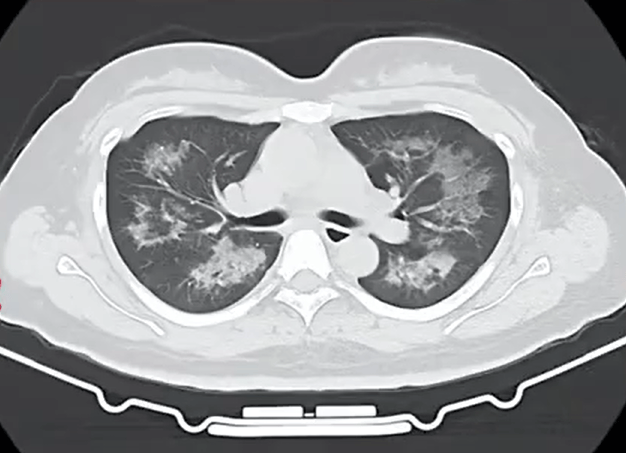

胸部CT进一步显示,她的双肺出现多发斑片状模糊影,被诊断为间质性肺炎币圈行业术语。医生判断,病因很可能与她近期长期接触的某类物质相关。经过医生反复细致地询问病史,小江才说出自己存在长期、频繁使用定妆喷雾的情况。